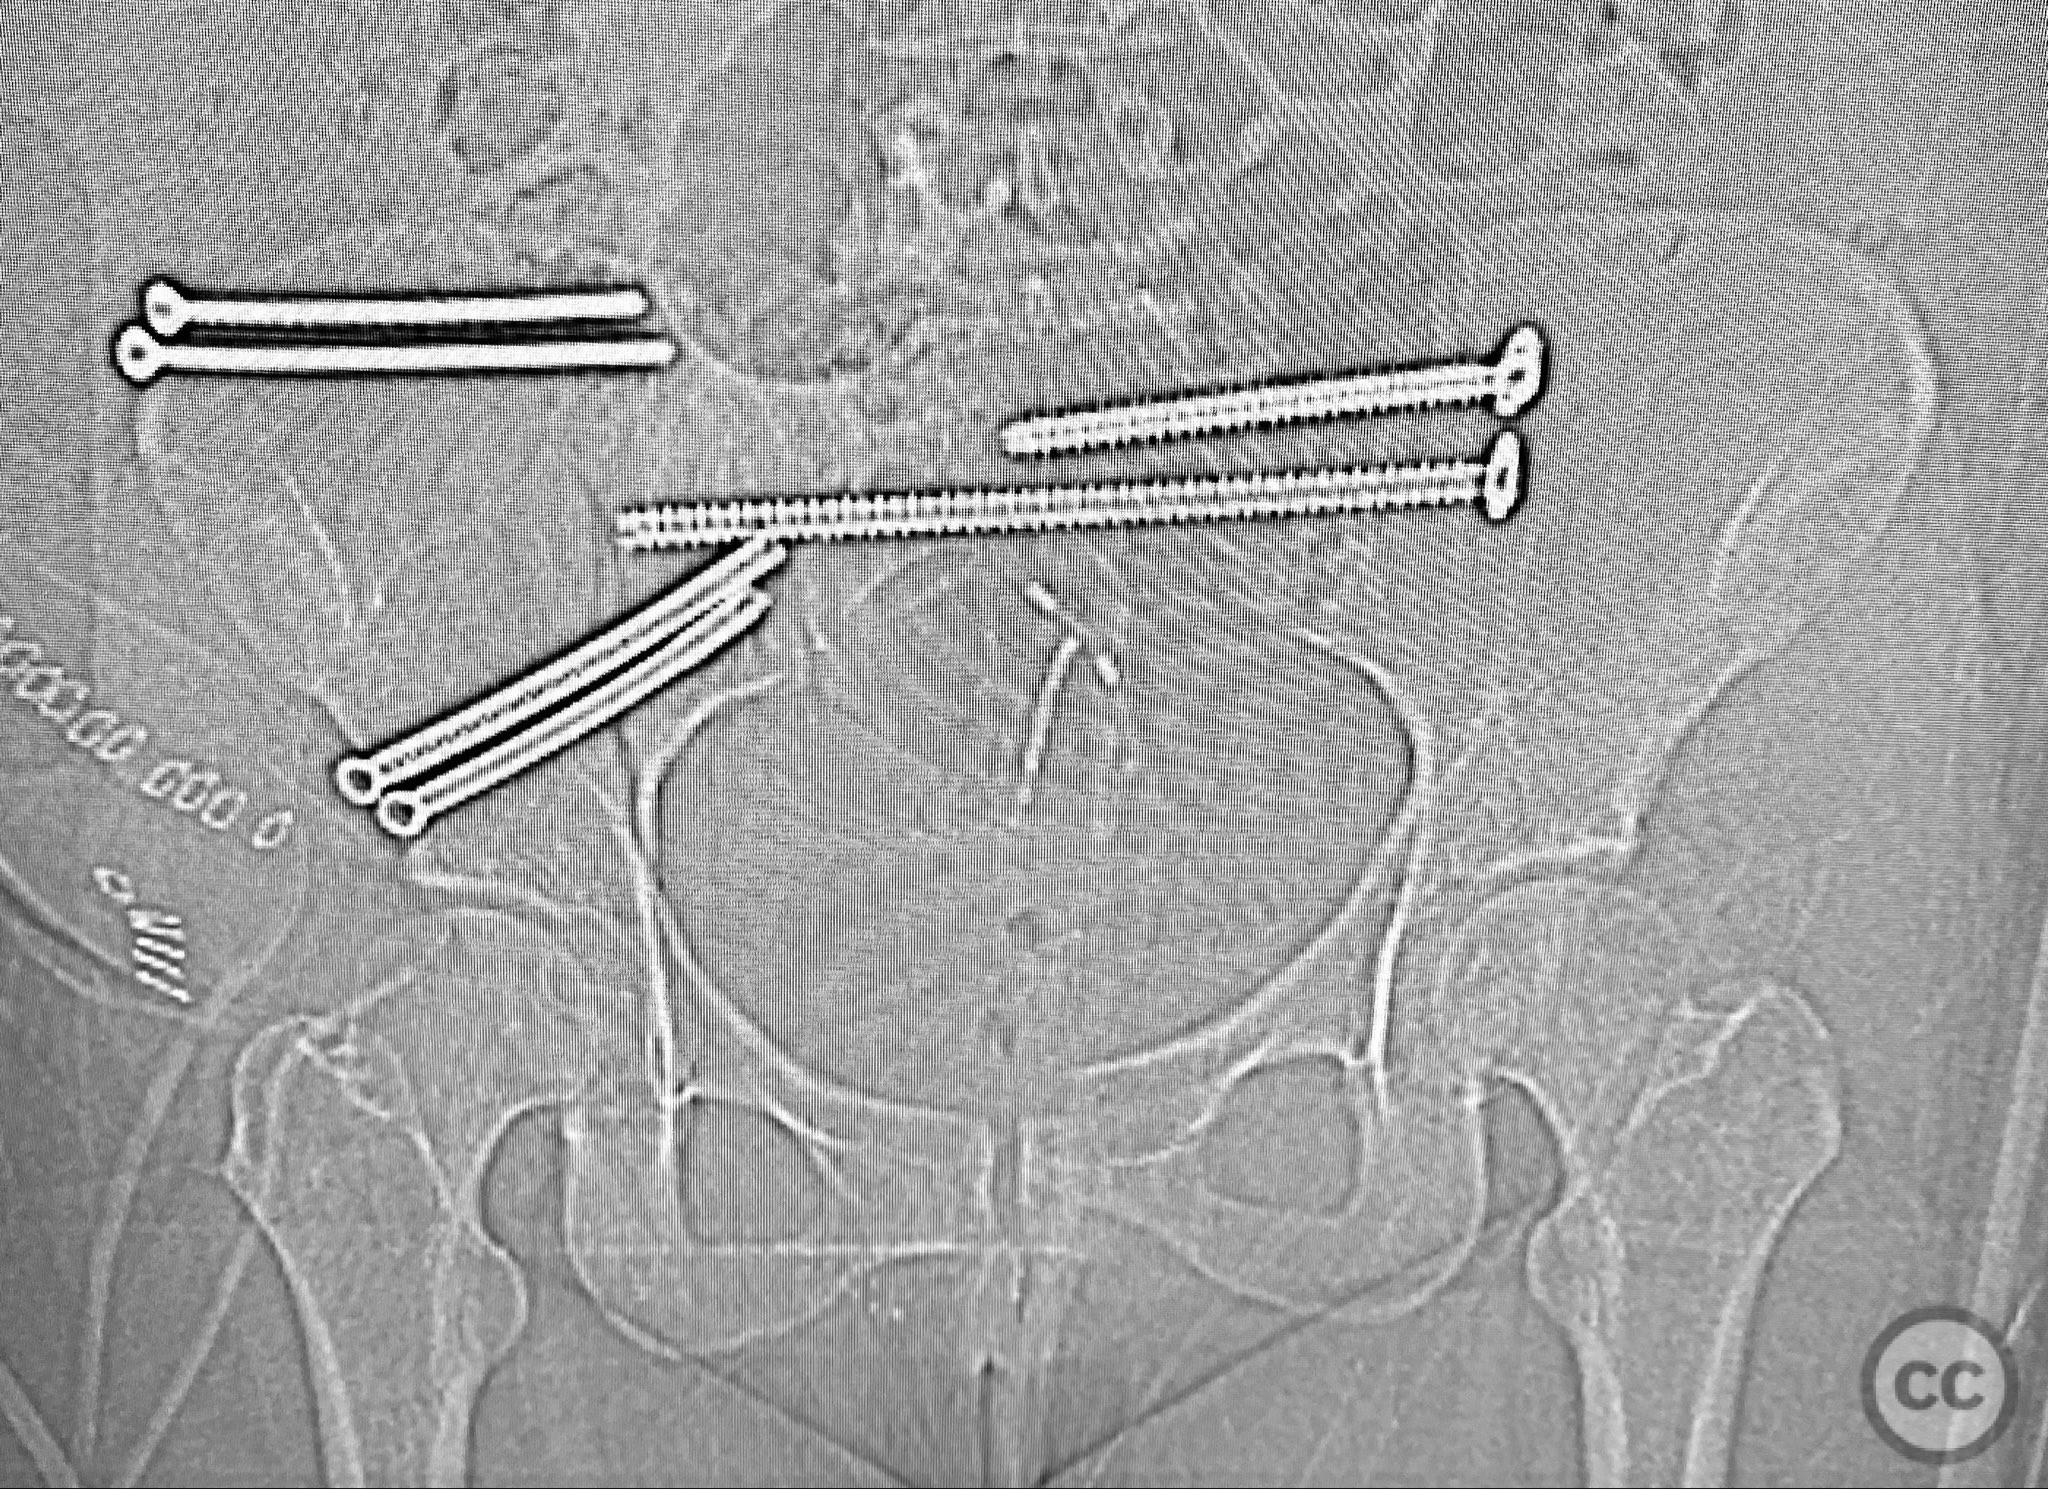

Anatomical surgical approach:  A standard anterior ilioinguinal approach was utilized for the right iliac fracture. Dissection proceeded through the skin and subcutis, with identification and protection of the lateral femoral cutaneous nerve. The external oblique aponeurosis was incised, and the iliacus muscle was elevated subperiosteally from the internal iliac fossa to expose the fracture site. Reduction was achieved under direct visualization, followed by internal fixation with a contoured plate and pelvic brim cancellous screws, ensuring all implants were contained within the osseous fixation pathway. The left sacral fracture was stabilized percutaneously under fluoroscopic guidance.

Bilateral distal femoral traction resulted in excellent reduction of the sacral fracture but did not adequately reduce the iliac displacement. Percutaneous fixation of the sacrum was performed first, followed by open reduction of the iliac fracture. Intraoperative imaging confirmed that all implants were fully contained within the available osseous corridors, avoiding extraosseous penetration. The complexity of the iliac fracture required careful anatomical reduction and implant placement along the pelvic brim.

Orthopaedic implants used:   Pelvic brim contoured plate, cancellous screws, percutaneous sacral screw(s)